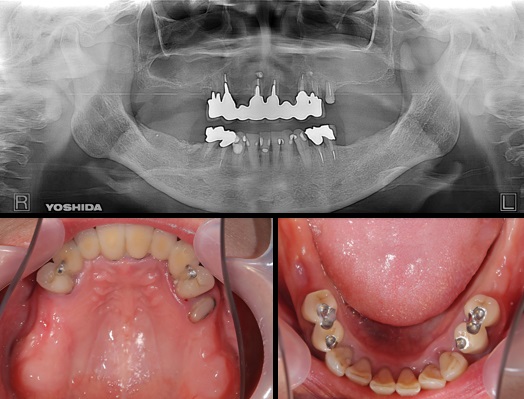

症例140代 男性 主訴 奥歯に歯を入れたい、しっかり噛みたい

治療前

治療後(5年経過)

主訴 奥歯がない為、食事が不自由である。入れ歯は煩わしいので、固定制のインプラントにして欲しいと訴え来院。口腔内全体で6本のインプラントを埋入。仮歯にて神経筋機構、顎関節のバランスを整え、リハビリを経て、約5ヶ月後にジルコニアを装着。

リスクとしては、外科的侵襲がある。デメリットは、保険外診療の為、経済的負担がある。

費用 316万(税込) (オペ・仮歯・最終補綴物まで含む)